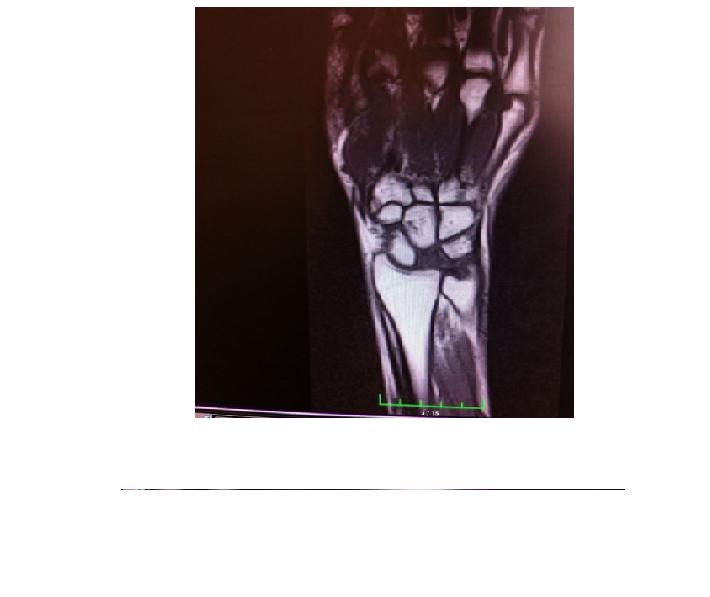

KİENBOCH HASTALIĞI

1910 yılında bir radyoloji doktoru olan Robert Kienboch tarafından tanım...

SKAFOİD KEMİK KIRIĞI

El bileğinde 2 sıra halinde bulunan 8 küçük kemikten bi...